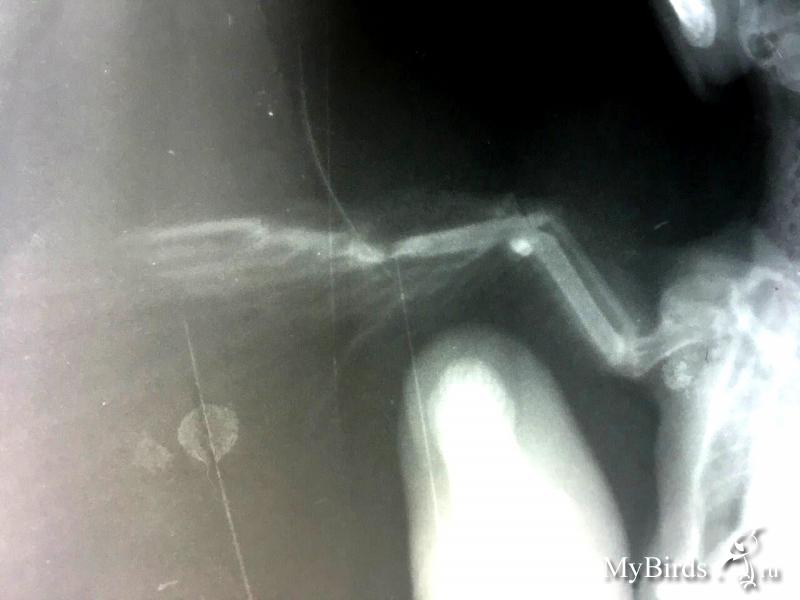

значительного смещения нет, шанс есть. но не 100%.

при таком переломе рентген в полной раскладке опасен( можно доломать, были случаи.

понятно... тогда половину написанного выше можно забыть. просто перед рентгеном крыло удачно сложили. собственно, стрижу с открытым переломом рентген делать особо незачем. разве что убедиться, что нет других повреждений.

птица не полетит. стрижи не летают после переломов со смещением. это пмж.